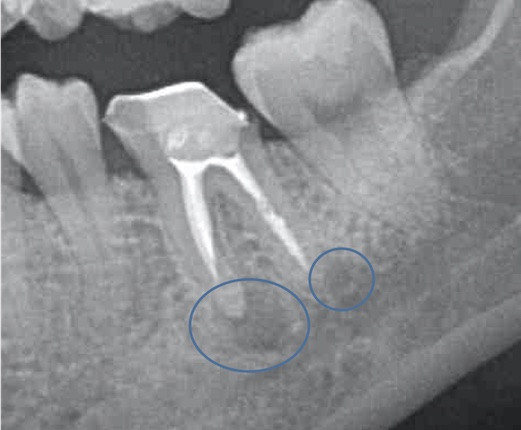

かぶせ物が不適であること(青矢印部)、近心根に根尖病巣があること(青枠部)、根充剤がかなり太いため(赤矢印部)歯質が薄くなっていることなど問題点がいくつかありましたが、他院で治療をしたばかりであり、また上記の条件から再治療には抜歯のリスクが非常に高いことから初診時は患者さんと相談し経過観察することになりました。